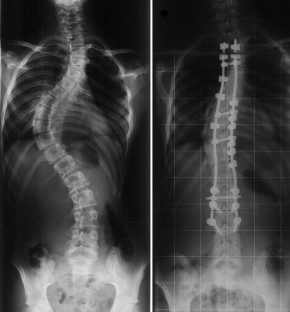

Correction of adolescent idiopathic scoliosis (AIS) has been reported with various systems. All-screw constructs are currently the most popular, but they have been associated with a significant decrease in thoracic kyphosis, with a potential risk of junctional kyphosis, not observed with hybrid constructs in the literature. In addition, it is important to weigh potential advantages of pedicle screw fixation against risks specific to its use. Because hybrid constructs are associated with a lower risk of complications and better sagittal correction than all-screw constructs, at present we use lumbar pedicle screws combined with a new sublaminar connection to the spine (Universal Clamps) at thoracic levels. The purpose of this study was to determine the efficacy and safety of the Universal Clamp (UC) posteromedial translation technique for correction of AIS. Seventy-five consecutive patients underwent posterior spinal fusion and hybrid instrumentation for progressive AIS. Correction was performed at the thoracic level using posteromedial translation. At the lumbar level, correction was performed using in situ contouring and compression/distractions maneuvers. A minimum 2-year follow-up was required. Medical data and radiographs were prospectively analyzed and compared using a paired t test. The average age at surgery was 15 years and 4 months (±19 months). The average number of levels fused was 12 ± 1.6. The mean follow-up was 30 ± 5 months. The average preoperative Cobb angle of the major curve was 60° ± 20°. The immediate postoperative major curve correction averaged 66 ± 13%. The average loss of correction of the major curve between the early postoperative assessment and latest follow-up was 3.5° ± 1.4°. The mean Cincinnati correction index was 1.7 ± 0.8 postoperatively, and 1.57 ± 1 at last follow up. The mean rotation of the apical vertebra was corrected from 23.3° ± 9° preoperatively to 7.3° ± 5° at last follow up (69% improvement, P < 0.0001). In the sagittal plane, the mean thoracic kyphosis improved from 23.8° ± 14.2° preoperatively to 32.3° ± 7.3° at last follow up. For the 68 patients who had a normokyphotic or a hypokyphotic sagittal modifier, thoracic kyphosis increased from 20.5° ± 9.9° to 31.8° ± 7.4°, corresponding to a mean kyphosis correction of 55% at last follow up. No intraoperative complication occurred and none of the patients developed proximal junctional kyphosis during the follow up. The principal limitation of the UC technique was the rate of proximal posterior prominence (14.6%), leading us to recommend the use of conventional claws at the upper extremity of the construct. The technique was safe, and reduced operative time, radiation exposure, and blood loss. While achieving correction of deformity in the coronal and axial planes equivalent to the best reported results of all-screw or previous hybrid constructs, the UC hybrid technique appears to provide superior correction in the sagittal plane. The excellent outcome in all three planes was maintained at 2 year follow up.

Fig. 1

Fig. 2